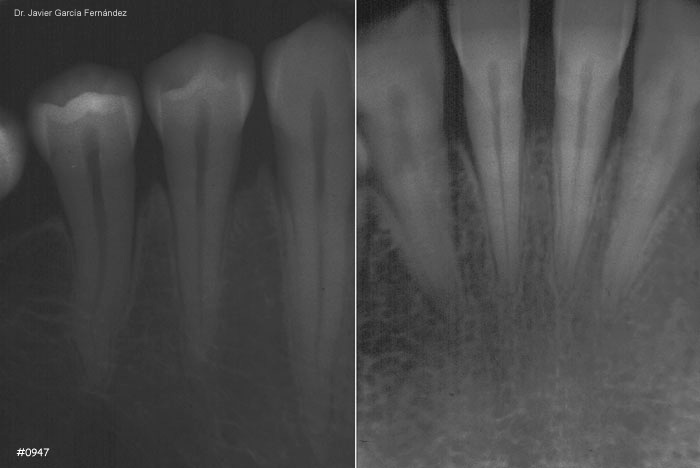

Atlas of Surgical Techniques in Periodontics. Chapter III. Atlas de Técnicas Quirúrgicas en Periodoncia